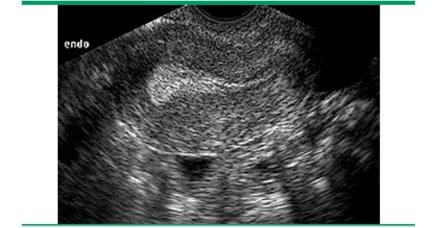

黄体期 — 排卵以后,「三线征」消失,取而代之的是一个10-14mm厚的强回声带。

一直到下次月经快来之前,内膜厚度可能达到18mm,甚至20mm左右的厚度。